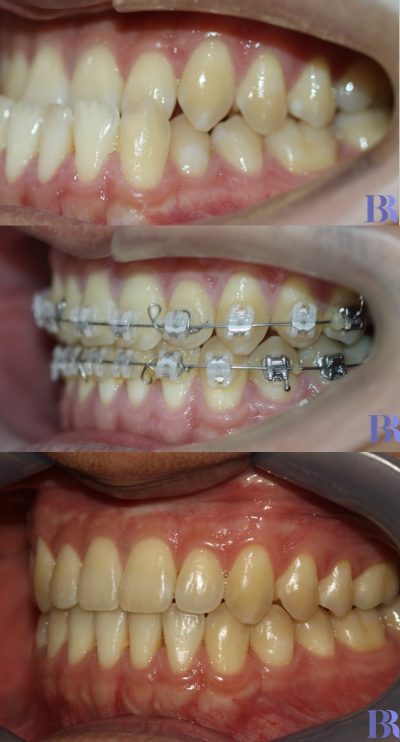

초진 입안사진입니다

치아가 거꾸로 물리고 있으나

실제 골격이 나온것에 비해서는

덜 나와 보이네요.

양악수술 대상자의 전형적인

치아 상태를 볼수 있습니다.

치성보상작용으로 인해

실제 골격에 비해 치아 간격이

좁아 보입니다

아랫니와 윗니 앞뒤 차이가

외모에 비해 심하지는 않습니다

치료 종료 후 입안을

촬영한 사진입니다

심미적일 뿐만 아니라

초진 시 보다 훨씬 더

건강해 보이지 않나요?

초진->수술직후->치료완료후

구내사진입니다.

정말 치료가 잘되었죠?

양악수술 전후 변화를

한눈에 보실 수 있습니다.